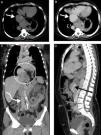

Computed tomography angiography of the chest, abdomen and pelvis, without contrast (A) and with contrast in the venous phase (B-D), showing aneurysmal dilatation of the proximal inferior vena cava next to its opening into the right atrium, reaching 56 mm in its largest diameter (A and B, straight white arrow). The middle, right and left hepatic veins drained into the aneurysmatic area, which was herniated into the thoracic region with part of the hepatic segment (C, white circle). Distal to the aneurysm, in the intrahepatic portion, the IVC was practically collapsed, with a very small caliber, for about 35 mm (D, black arrow). In the subhepatic region, into which the other abdominal and pelvic veins drained, the IVC had a normal appearance and caliber (C, curved white arrow).

A 62-year-old woman undergoing control exams following resection of a left renal tumor two years previously reported only dyspnea on moderate to strenuous exertion. Computed tomography (CT) angiography of the chest, abdomen and pelvis revealed an idiopathic aneurysmal dilatation of the proximal inferior vena cava (IVC) next to the right atrium, 56 mm on its largest axis (type I in the Gradman and Steinberg classification) (Figure 1). The middle, right and left hepatic veins drained into the aneurysmatic area, which was herniated into the thoracic region with part of the hepatic segment. Distal to the aneurysm, in the intrahepatic portion, the IVC was practically collapsed, with a very small caliber, for about 35 mm. In the subhepatic region, into which the other abdominal and pelvic veins drained, the IVC had a normal appearance and caliber.